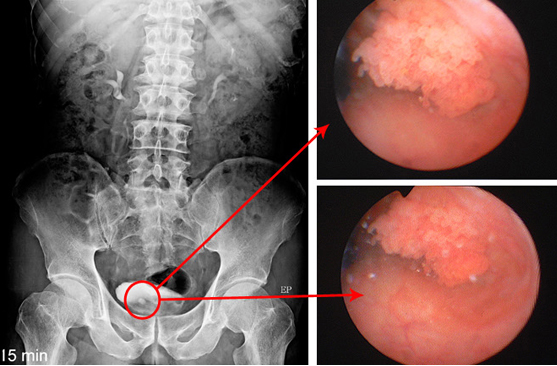

01방사선 검사는 X-ray 촬영을 통해 신장, 요관, 방광을 검사합니다.

03무통 연성 전자 내시경

(요도 안쪽으로 마취제 를 도포하고 요도를 통해 무통 연성 전자 내시경을 삽입한 뒤, 요도와 전립선, 방광 중에서검사하고자 하는 부위를 검사합니다.)

전자내시경은 특히 원인을 알 수 없는 육안적 및 현미경적 혈뇨진단에 유용한데

직접적인 전자내시경을 통해 발병 원인을 찾아낼 수 있는 정밀검사법입니다.

방광결석

방광암